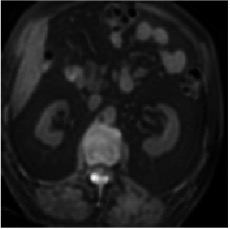

This work presents a novel framework CISFA (Contrastive Image synthesis and Self-supervised Feature Adaptation)that builds on image domain translation and unsupervised feature adaptation for cross-modality biomedical image segmentation. Different from existing works, we use a one-sided generative model and add a weighted patch-wise contrastive loss between sampled patches of the input image and the corresponding synthetic image, which serves as shape constraints. Moreover, we notice that the generated images and input images share similar structural information but are in different modalities. As such, we enforce contrastive losses on the generated images and the input images to train the encoder of a segmentation model to minimize the discrepancy between paired images in the learned embedding space. Compared with existing works that rely on adversarial learning for feature adaptation, such a method enables the encoder to learn domain-independent features in a more explicit way. We extensively evaluate our methods on segmentation tasks containing CT and MRI images for abdominal cavities and whole hearts. Experimental results show that the proposed framework not only outputs synthetic images with less distortion of organ shapes, but also outperforms state-of-the-art domain adaptation methods by a large margin.